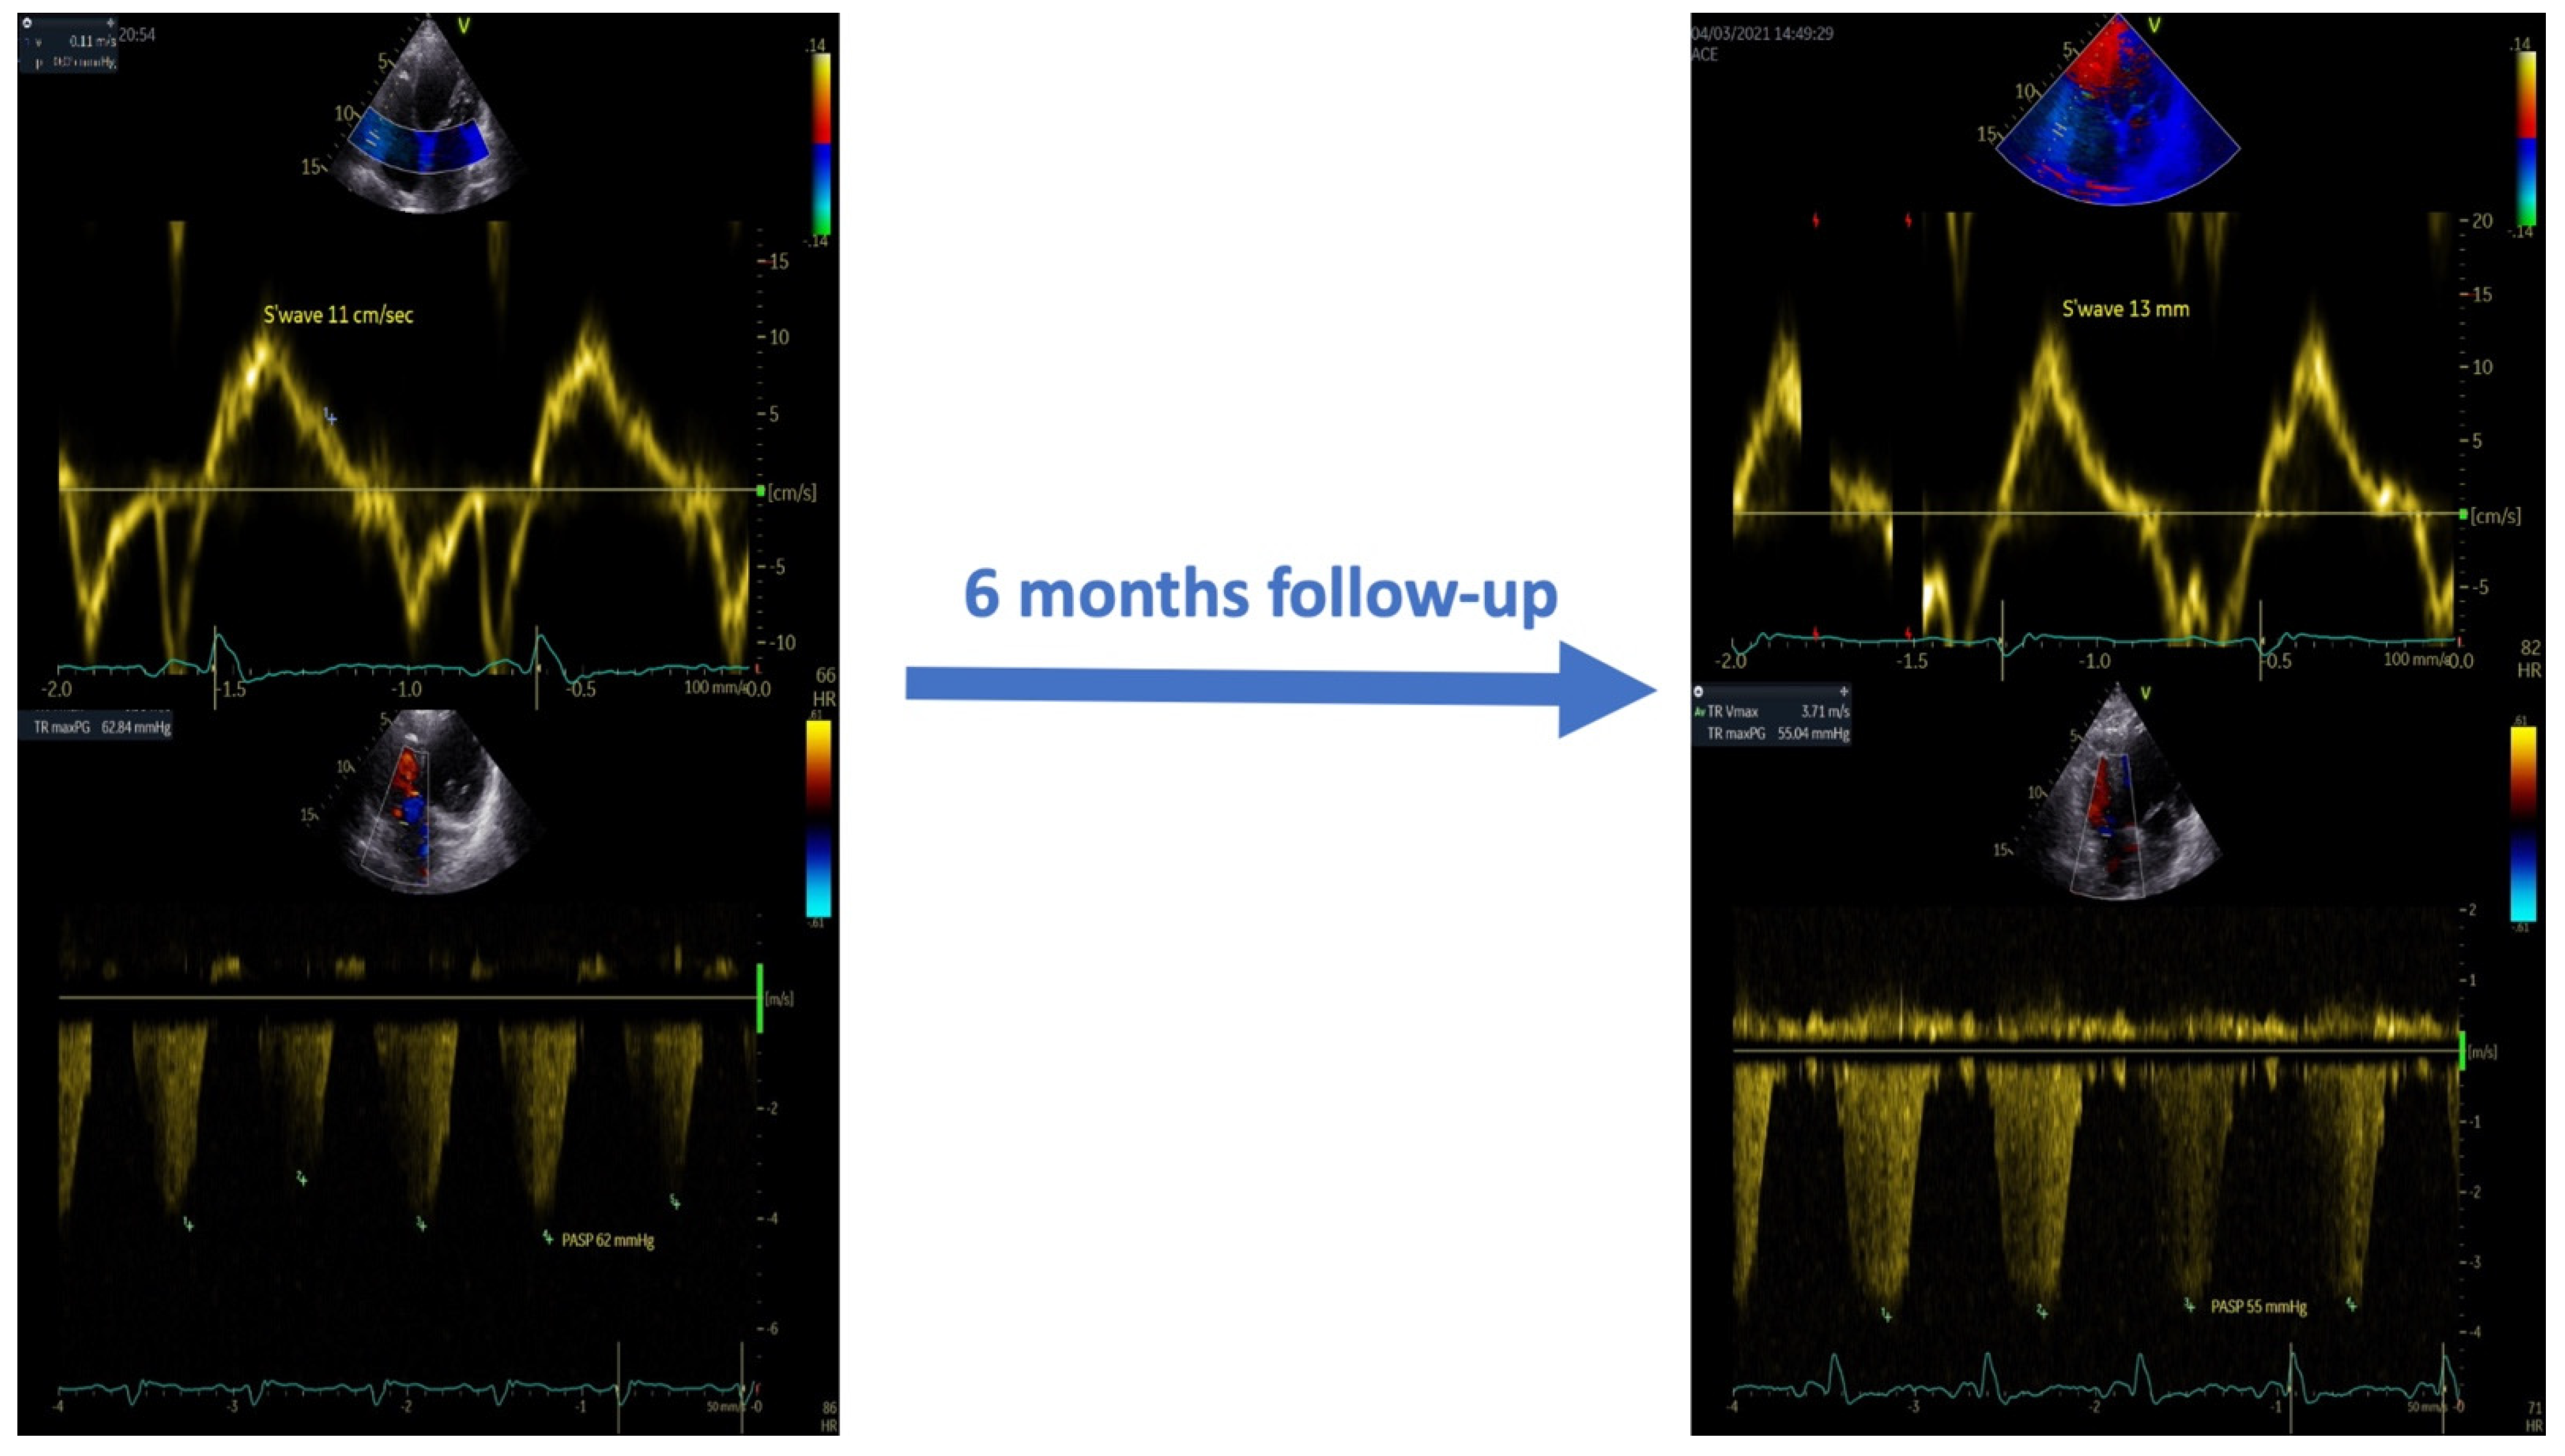

In addition, as shown in Table 2 and Figure 3, at the six-month follow-up, the CCM therapy induced right ventricular reverse remodeling and reduced systolic pulmonary pressure values.

Figure 3.

Effects of CCM therapy on the systolic function and pulmonary artery systolic pressure at the six-month follow-up.